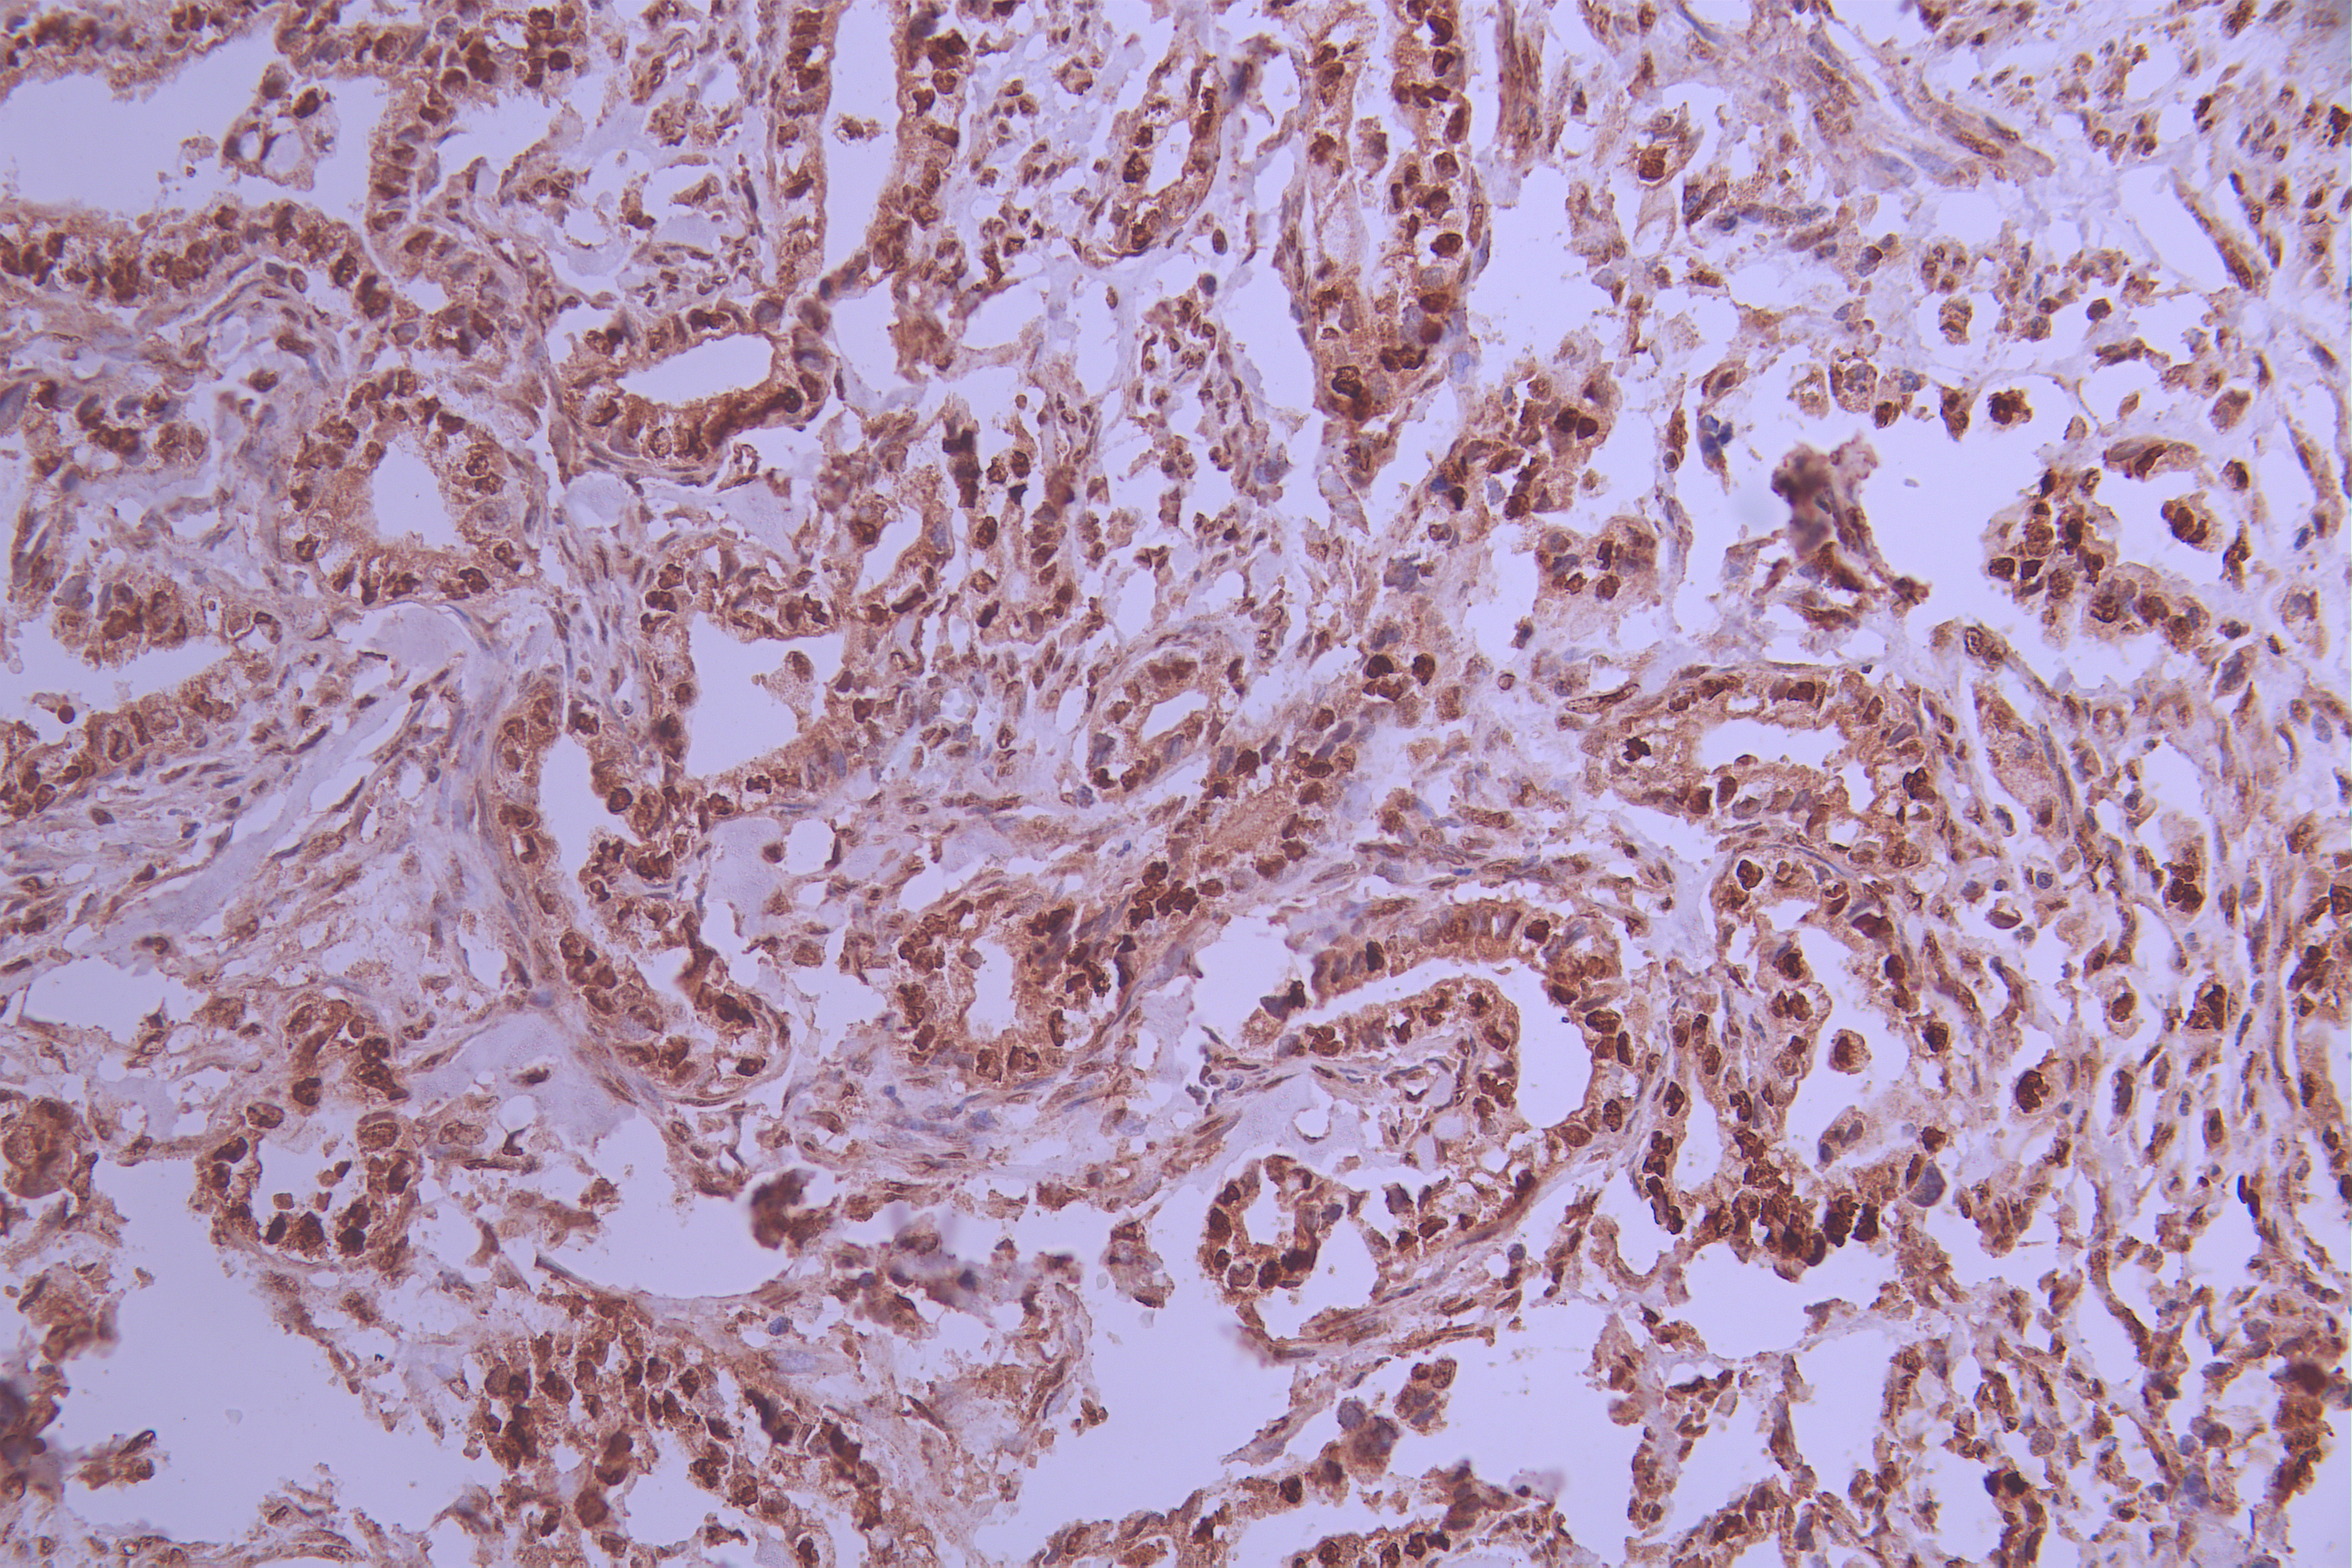

IHC image of CSB-RA586611A0HU diluted at 1:100 and staining in paraffin-embedded human placenta tissue performed on a Leica BondTM system. After dewaxing and hydration, antigen retrieval was mediated by high pressure in a citrate buffer (pH 6.0). Section was blocked with 10% normal goat serum 30min at RT. Then primary antibody (1% BSA) was incubated at 4°C overnight. The primary is detected by a Goat anti-rabbit polymer IgG labeled by HRP and visualized using 0.05% DAB.